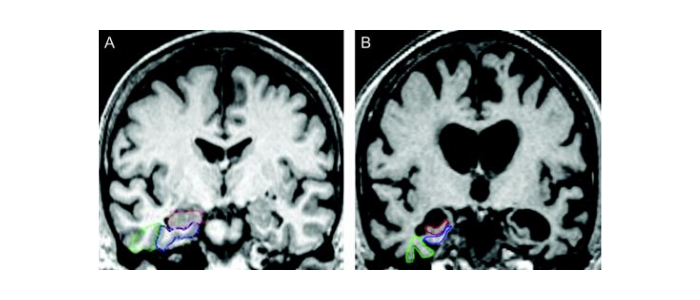

Researchers performed a post-treatment MRI on the brain of each participant. The MRI revealed that the blood-brain barrier opened within the target areas after the ultrasound treatment and then closed after 24 hours.

The authors went on to explain the process behind the new ultrasound treatment. LIFU consists of placing a helmet over the patient’s head after they are positioned in the MRI scanner. This helmet is then equipped with more than a thousand separate ultrasound transducers pointing in different directions. Each transducer delivers sound waves which are directed to a target area of the brain. During the procedure, patients are given an ultrasound contrast agent intravenously that is made up of microbubbles. These go changing in size and shape as the ultrasound is applied. Dr. Mehta said this oscillation results in transient loosening of the blood-brain barrier, which they documented using gadolinium contrast enhanced MRI.